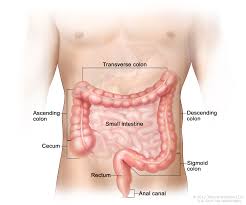

Abdominal and Pelvic Anatomy The cecum measures approximately 5 to 7 cm in length and directly communicates with the terminal ileum at the ileocecal valve. The cecum can be partly or completely mobile along its mesentery, sometimes resulting in cecal volvulus.

The cecum, pronounced “see-kum,” is also called the “proximal right colon.” It is a small pouch that measures about 6 by 9 centimeters (cm) , or about 2.3 by 3.5 inches (in). The cecum is held by a thin membrane known as the peritoneum. This pouch connects the small intestine to the rest of the colon.

Is the cecum on the left or right?

The cecum or caecum is a pouch within the peritoneum that is considered to be the beginning of the large intestine. It is typically located on the right side of the body (the same side of the body as the appendix, to which it is joined).

What organ is attached to the cecum?

The cecum is the proximal blind pouch of the ascending colon, lying at the level of the ileocecal junction. The terminal ileum opens into the cecum on the medial wall, and the ileocecal valve guards this opening. The appendix is a thin cylindrical organ with a blind attachment to the cecum.

How important is the cecum?

The main functions of the cecum are to absorb fluids and salts that remain after completion of intestinal digestion and absorption and to mix its contents with a lubricating substance, mucus. The internal wall of the cecum is composed of a thick mucous membrane, through which water and salts are absorbed.